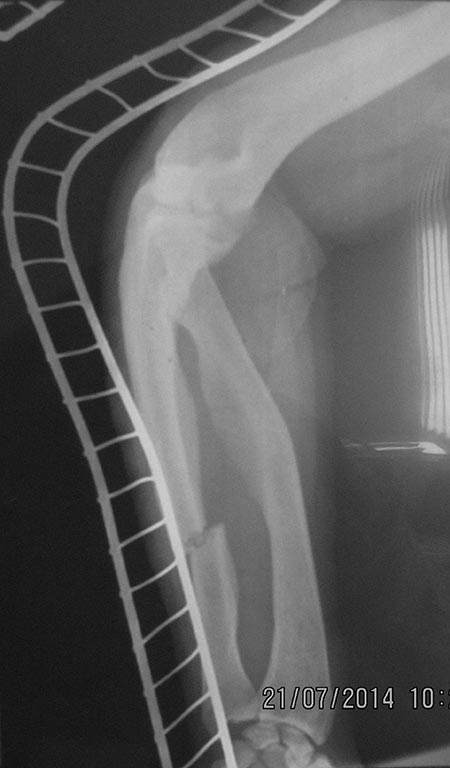

Re: перелом бедра с исходной деформацией

For Maxim,

Выкладываю, как и обещал. За репозицию педплечья не осуждайте!